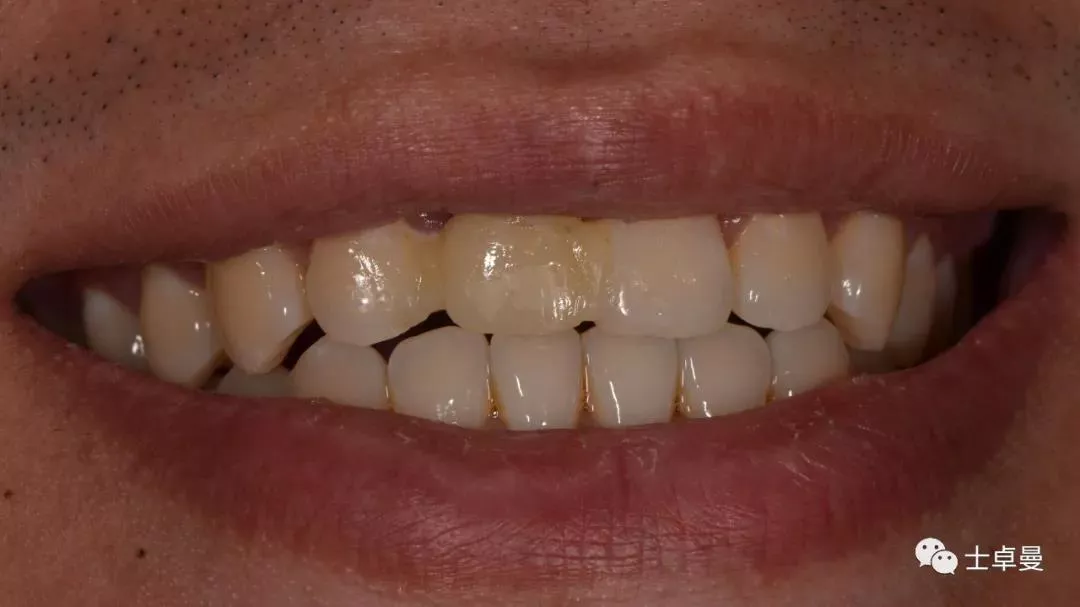

初诊情况

· 主诉:门牙外伤冠折后2月就诊

· 现病史:2月前患者门牙外伤折断,已于我院牙体牙髓科完成根管治疗,但因断冠粘接反复脱落,正畸会诊后示残根牵引将导致冠根比例失调,效果不佳,要求拔除后行种植义齿修复。

口内检查

· 11牙冠折断,余留残根;

· 唇侧位于龈上2mm,腭侧达骨下1mm,根管内封药存;

· 探(-),冷 (无反应),叩 (-),松 (-),牙龈可;

· 中位笑线,牙龈生物型为中弧形、中厚龈生物型;

· 其余牙及口腔卫生尚可。